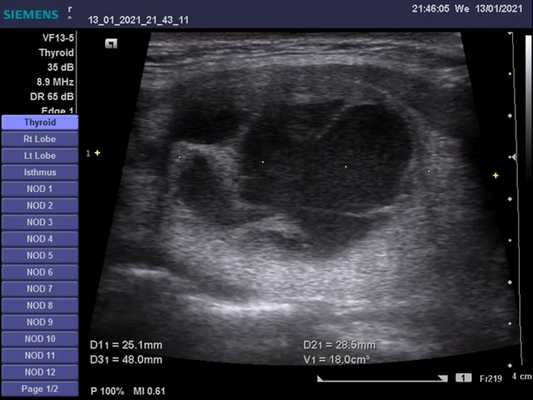

УЗИ можно использовать для визуализации умеренно увеличенной щитовидной железы с характерной слабой эхогенностью, однородным или слегка неоднородным рисунком, соответствующим гистологически гиперпластическим, но пустым фолликулам.

Цветовые и энергетйические допплеровские исследования демонстрируют поразительную гиперваскулярность. Поток в питающих артериях быстрый, более 100 см/с; снижение до менее 40 см/с при лечении интерпретируется как признак хорошего прогноза. Очаговые поражения (узлы) в щитовидной железе с плохим эхо-сигналом при болезни Грейвса-Базеда не зависят от основного заболевания и должны рассматриваться отдельно.

- Легкое / умеренное диффузное, симметричное увеличение щитовидной железы, включая перешеек на УЗИ

- Увеличение в объеме щитовидной железы ≤ 90 мл

- Картина эхоструктуры паренхимы: гипоэхогенная, гетерогенная, «пятнистая»

- Гипоэхогенность паренхимы обусловлена уменьшением коллоидного содержимого и увеличение клеточного состава с уменьшением коллоидно-клеточного соотношения ± гиперваскулярность

- На УЗИ с ЦДК отмечается увеличение кровотока в паренхиматозной сосудистой системе (турбулентный кровоток с артериовенозными шунтами): «ад щитовидной железы»

- Спектральный допплер: увеличение пиковой скорости кровотока (≤ 120 см / сек), в измеренной нижней щитовидной артерии

Лучший диагностический метод при данной патологии - УЗИ. На нем регистрируется увеличенная железа, гипоэхогенная, гетерогенная картина ее внутренней эхоструктуры и увеличение паренхиматозной васкуляризации. Размер щитовидной железы имеет легкое или умеренное увеличение в размере. Как проводят ультразвуковую диагностику при болезни Грейвса? Необходимо использовать преобразователь с высоким разрешением, частота сканирования ≥ 7,5 МГц. Сканирование в продольной и поперечной плоскостях, включая доплеровское исследование.

Серошкальное УЗИ при болезни Грейвса. Легкое или умеренное диффузное, симметричное увеличение щитовидной железы, включая перешеек. Увеличение в объеме щитовидной железы ≤ 90 мл. Нормальный объем: новорожденный 0,4-1,4 мл, увеличение на 1,0-1,3 мл на каждые 10 кг веса, до нормального объема 10-11 (± 3-4) мл у взрослых. Гипоэхогенный, гетерогенный, «пятнистый» паттерн паренхиматозной эхоструктуры. Гипоэхогенность паренхимы обусловлена снижением коллоидного содержимого и увеличением клеточного состава с уменьшением коллоидно-клеточной границы ± гиперваскулярность. Гипоэхогенность паренхимы связана с частотой позитивности антител к рецептору ТТГ (TRAb). Сохранение гипоэхогенности паренхимы при прекращении лечения, связанного с рецидивом гипертиреоза